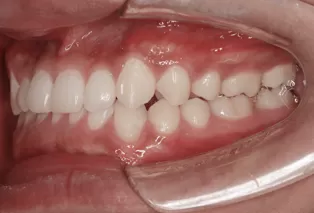

Intraoral photos after treatment